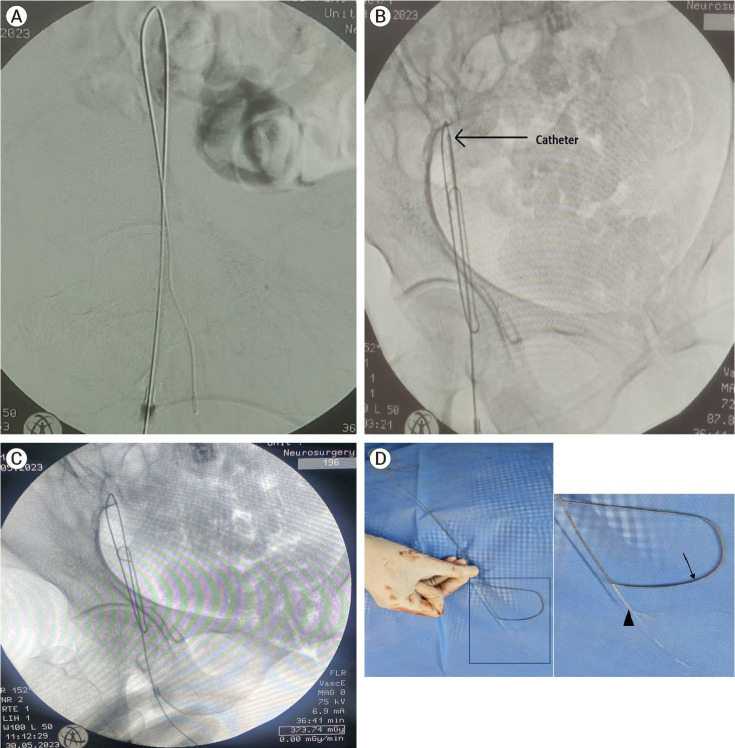

Percutaneous techniques for femoral arterial access are increasingly being performed due to advances in endovascular cerebral procedures, as they provide a less morbid and minimally invasive approach than open procedures. Common complications associated with this peripheral puncture include hematoma, bleeding, pseudoaneurysm, arteriovenous fistula, retroperitoneal bleeding, inadvertent venous puncture, dissection, etc. The retrograde femoral access is currently the most frequently used arterial access as it is technically straightforward, allows for the use of larger size sheaths and catheters, allows repeated attempts, etc. Although being technically less challenging, grave complications can occur due to hardware failure. Here, we present a case of unruptured posterior inferior cerebellar artery (PICA) aneurysm, who underwent uneventful diagnostic cerebral digital substraction angiography (DSA) via right femoral artery route on first attempt, but on second attempt for therapeutic intervention, landed up with stuck guide wire and faced decannulation difficulty due to unravelling of guide wire and multiple knot formation, which was finally removed after multiple attempts at pulling and improvised manoeuvres. Such cannulation and decannulation difficulties have been reported multiple times for central venous access, but extremely rarely for femoral routes, making this case a rarity and worth reporting.